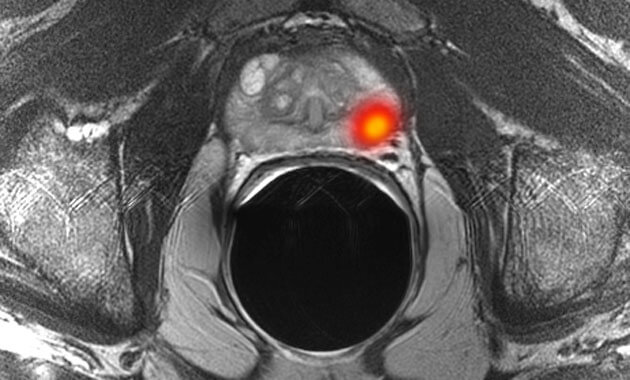

The Abdominal Imaging Division of the UC San Francisco Department of Radiology and Biomedical Imaging is made up of internationally recognized abdominal imaging experts who diagnose and treat disorders of the liver, pancreas, colon, uterus, ovaries, prostate, and bladder. The Abdominal Imaging Division is focused on serving patients, conducting research, and training the next generation of radiologists.

- Prostate tumors/cancer